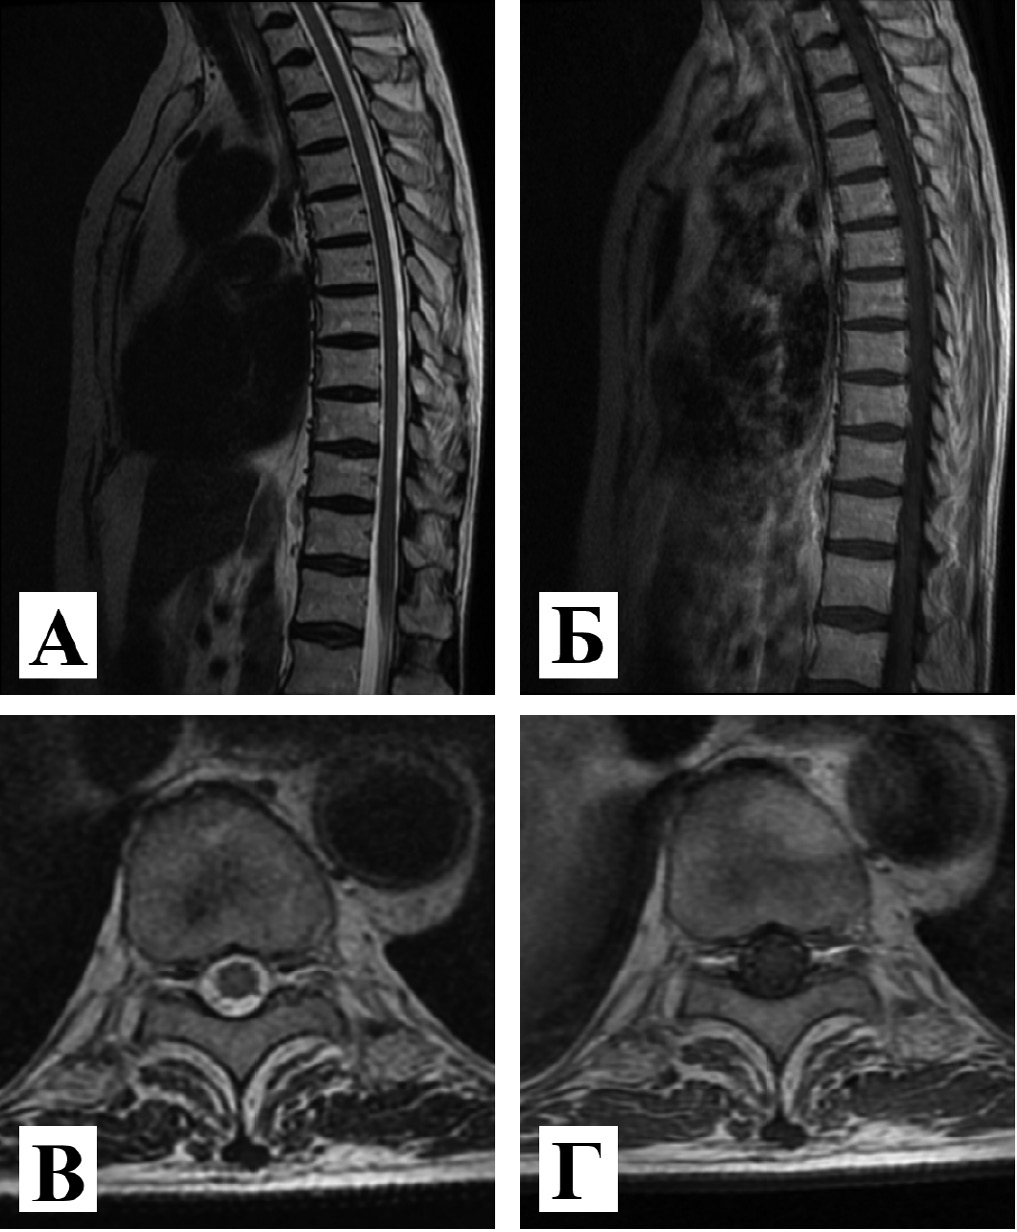

1. Рис. 1. МРТ грудного отдела спинного мозга с контрастным усилением, 3 Тл. Сагиттальная проекция в режимах: А - Т2-FLAIR; Б – Т1 с контрастным усилением. Аксиальная проекция на уровне Th-10 в режимах: В - Т2-FLAIR; Г –Т1 с контрастным усилением. МР-сигнал от спинного мозга не изменен, структура спинного мозга однородная. Патологического накопления контрастного препарата не выявлено. | |